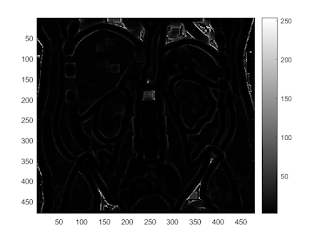

prewitt edge filter

b = fspecial('prewitt'); I2 = conv2(I,b.','same'); imagesc(abs(I2)); colorbar caxis([0,300])

imagesc(abs(I2)>150)

sobel edge filter

b = fspecial('sobel'); I2 = conv2(I,b,'same'); imagesc(I2); colorbar

imagesc(abs(I2)>200)

standard deviation edge filter

I2 = nlfilter(I, [3,3], 'std2');

imagesc(I2);

colorbar;

imagesc(I2>10);